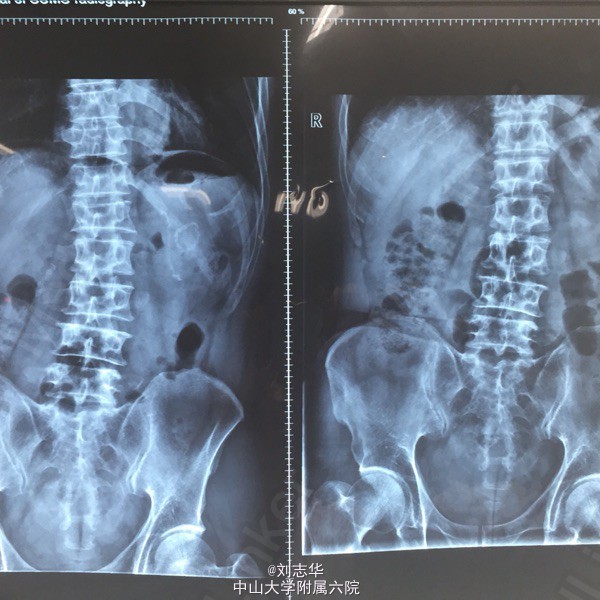

患者男,64岁,两年前于外院因"胃溃疡穿孔"行"胃大部切除术"。一天前无明显诱因出现上腹疼痛,程度剧烈,刀割样,急诊行腹平片检查:双膈下游离气体。

查体:上腹部10cm手术疤痕,全腹压痛反跳痛明显。肠鸣音1-2次/分。余无特殊。 腹平片:双膈下游离气体。